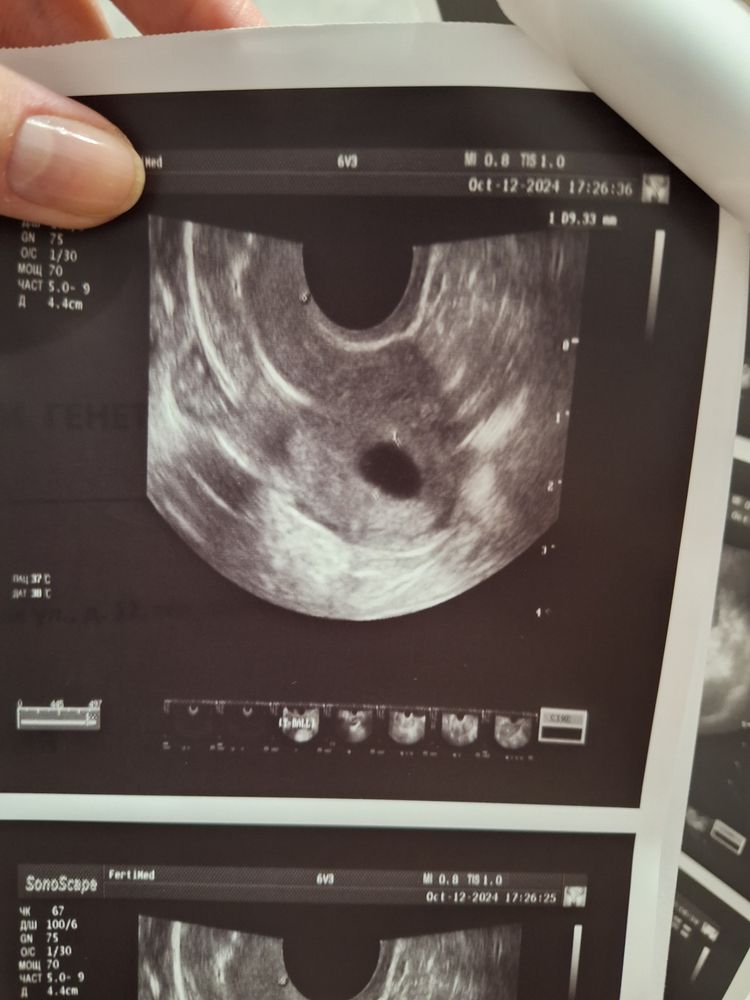

В октябре прошла ГСГ эхо в фертимед , врач прямым текстом сказала- трубы не прлходимы, вообще, жидкость стоит в углах матки и ни на мм в трубы не заходит. Нафоткала узи, дала заключение. С ним я поехала к репродуктологу в МиД, выбирала по отзывам, доктор очень мне понравилась. Она взяла снимки узи и первое что сказала- как не прлходимы? Вот же жидкость, до середины. А дальше либо не сфоткали, либо неизвестно. В общем я в шоке. Я читала и про спазм труб, и что бывают ошибки, но чтоб вот так? Человек который делал гсг и своими глазами смотрел просто не увидел что жидкость проходит? Даже до середины. Все же это совсем не " не прлходит, стоит в матке" Поговорите со мной.